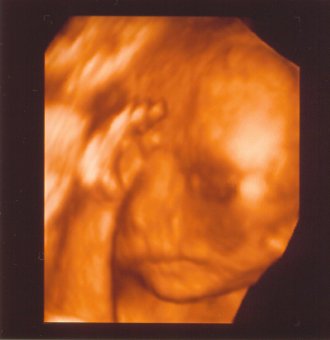

Ő Jázmin! Rengeteget mocorgott, mosolygott, dörzsölte a szemét. Lehet épp akkor ébredezett! Lehetett látni, ahogy iszik a magzatvízből, bevette a szájába az ujját. Nagyon édes volt! A doki megdícsért, hogy szépen fejlődik a baba. 400 grammos! Hihetetlen!

Ő Jázmin! Rengeteget mocorgott, mosolygott, dörzsölte a szemét. Lehet épp akkor ébredezett! Lehetett látni, ahogy iszik a magzatvízből, bevette a szájába az ujját. Nagyon édes volt! A doki megdícsért, hogy szépen fejlődik a baba. 400 grammos! Hihetetlen!